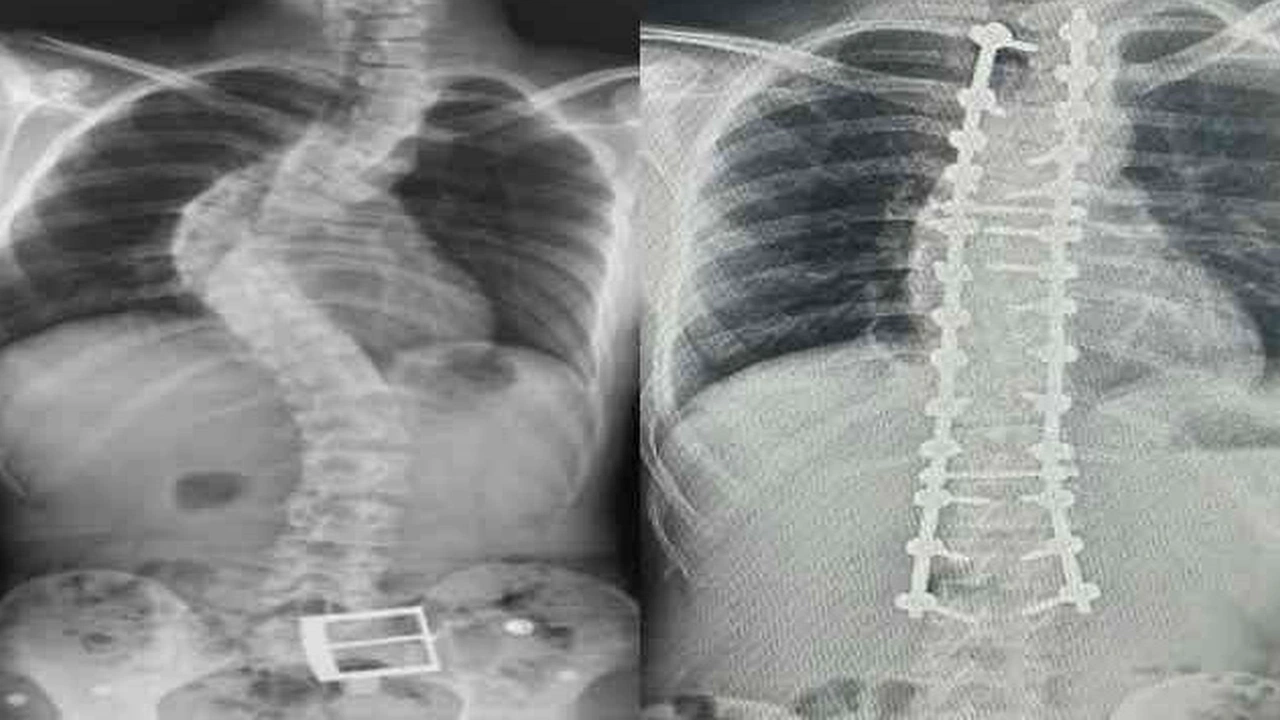

Dr. Yüksel, erken teşhis sonrası tedavi sürecinin korkulacak bir süreç olmadığını belirtti. "10-20 derece arası eğriliklerde özel egzersizler ve takip yeterli oluyor. 20-40 derece arasında ise egzersize ek olarak korse tedavisi uyguluyoruz. 40 derecenin üzerindeki ileri vakalarda ise cerrahi yöntemler gündeme geliyor," diyerek tedavi yol haritasını özetledi.